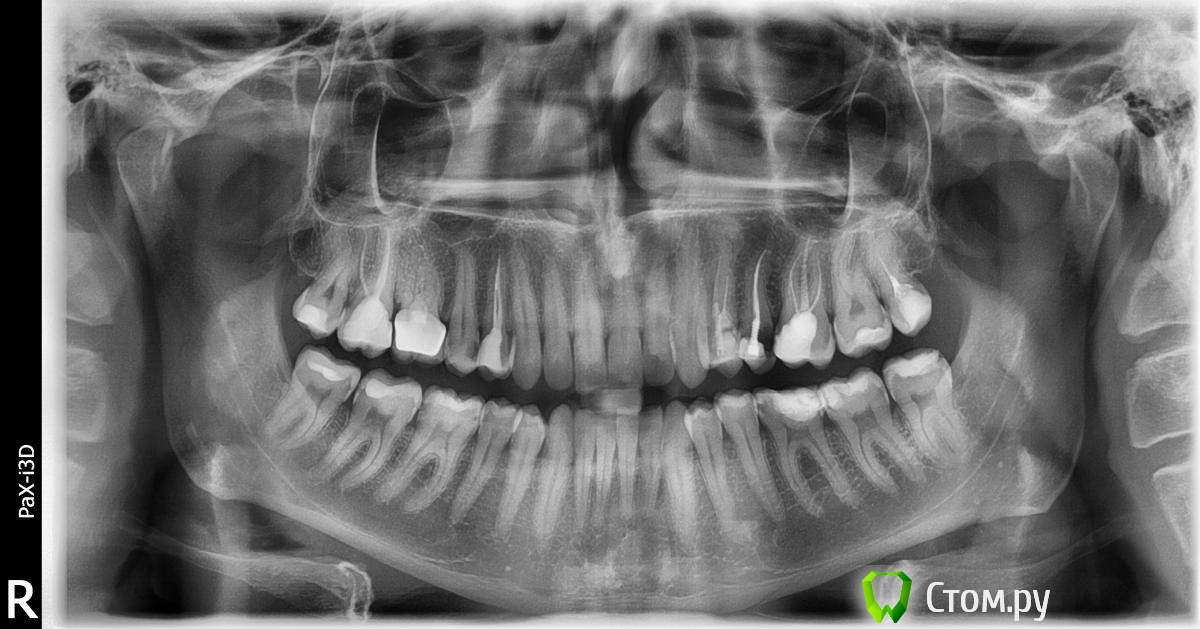

diesel87 Опубликовано 23 августа, 2014 Поделиться Опубликовано 23 августа, 2014 Кариес на 15, 37, 36, возможно на 35, 45, 46, возможно 47, 48На все зубы где пролечены каналы коронки с вкладками, кроме восьмерок. Ссылка на комментарий

faity Опубликовано 24 августа, 2014 Поделиться Опубликовано 24 августа, 2014 +1, от себя добавлю 2.5 под вопросом, нужно очно смотреть насколько глубоко разрушен Ссылка на комментарий